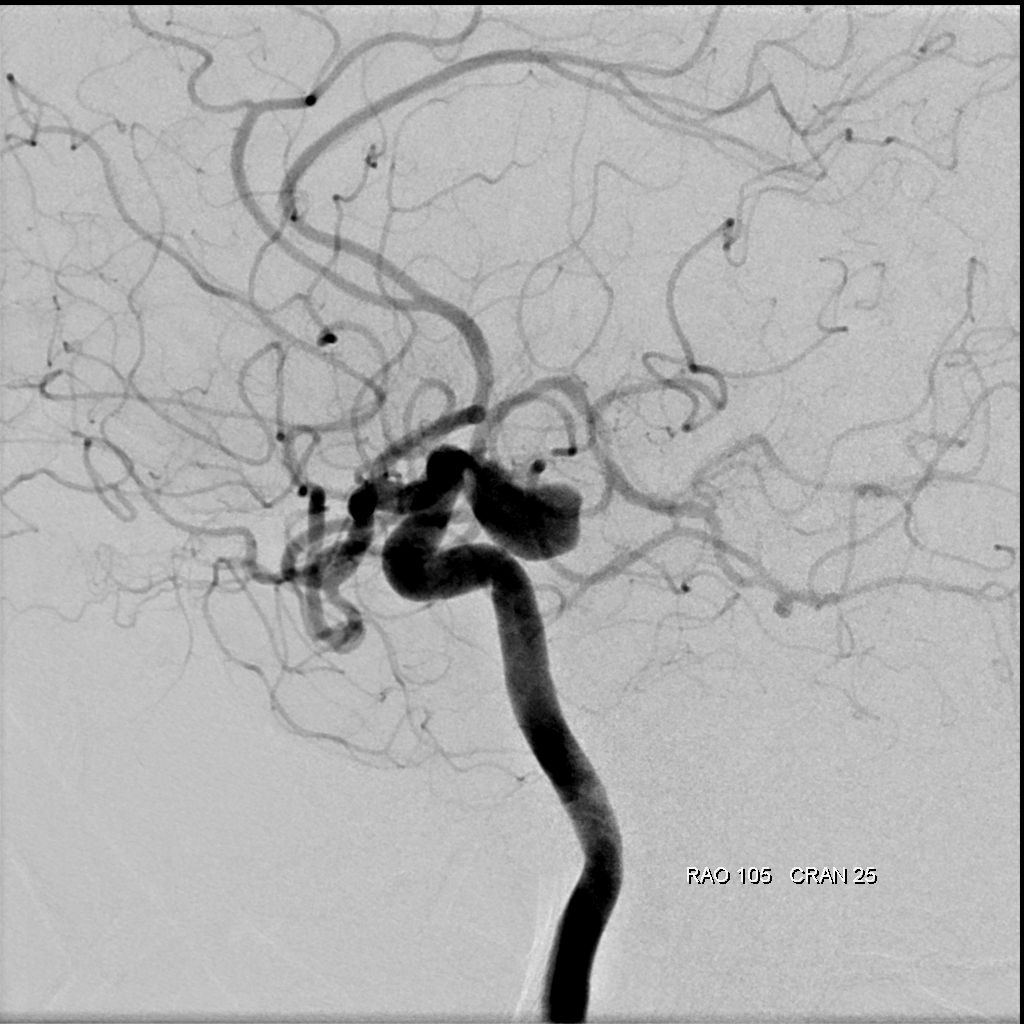

アンギオ装置

肘や太ももの付け根の動脈からカテーテルと呼ばれる細い管を挿入し、造影剤という薬剤を流し込みながら X 線撮影を行うことで、血管の状態や、流れを観察する検査です。

これにより血管にできたコブ(動脈瘤)、血管の狭窄、血管奇形、腫瘍などをより正確に把握し、今後の治療方針の検討を行います。

当院のアンギオ装置Artis zeeはフラットパネル血管造影システムにより、従来装置と比較して約50%の被曝量削減を実現しています。また3D撮影することにより的確な画像を提供することができます。

当院では必要に応じて脳血管内治療(IVR)も行います。

脳動脈瘤のコイル塞栓術や、脳血管の狭窄に対するステント留置術など、IVR(インターベンショナル・ラジオロジー:)と呼ばれる血管内治療に対応しています。

脳血管画像

脳血管3D画像

脳血管内治療WovenEndoBridgeデバイス(WEB)